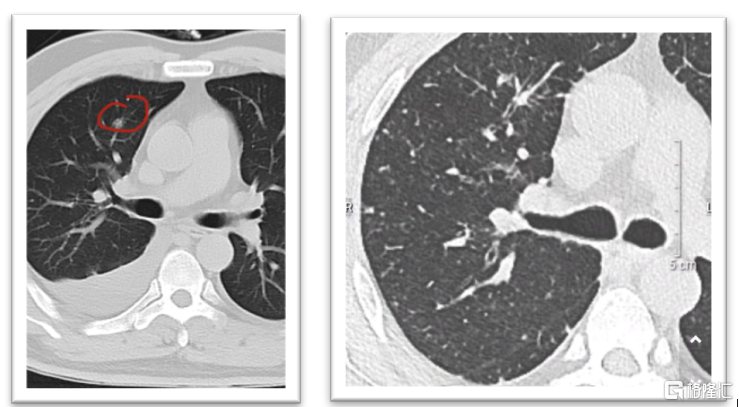

另一名接受临床试验的患者的治疗过程同样非常顺利,治疗全程未发生与药物相关的SAE。治疗期间患者进行了2次肿瘤评估,疗效评价均为PR,且首次肿瘤评估,肺转移灶即消失,展现了KN046联合一线治疗的潜力。

图表三:患者胸部CT平扫对比

数据来源:公司资料,格隆汇整理